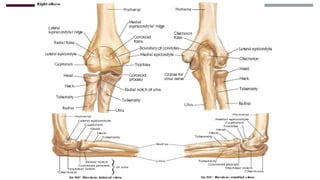

ANATOMÍA